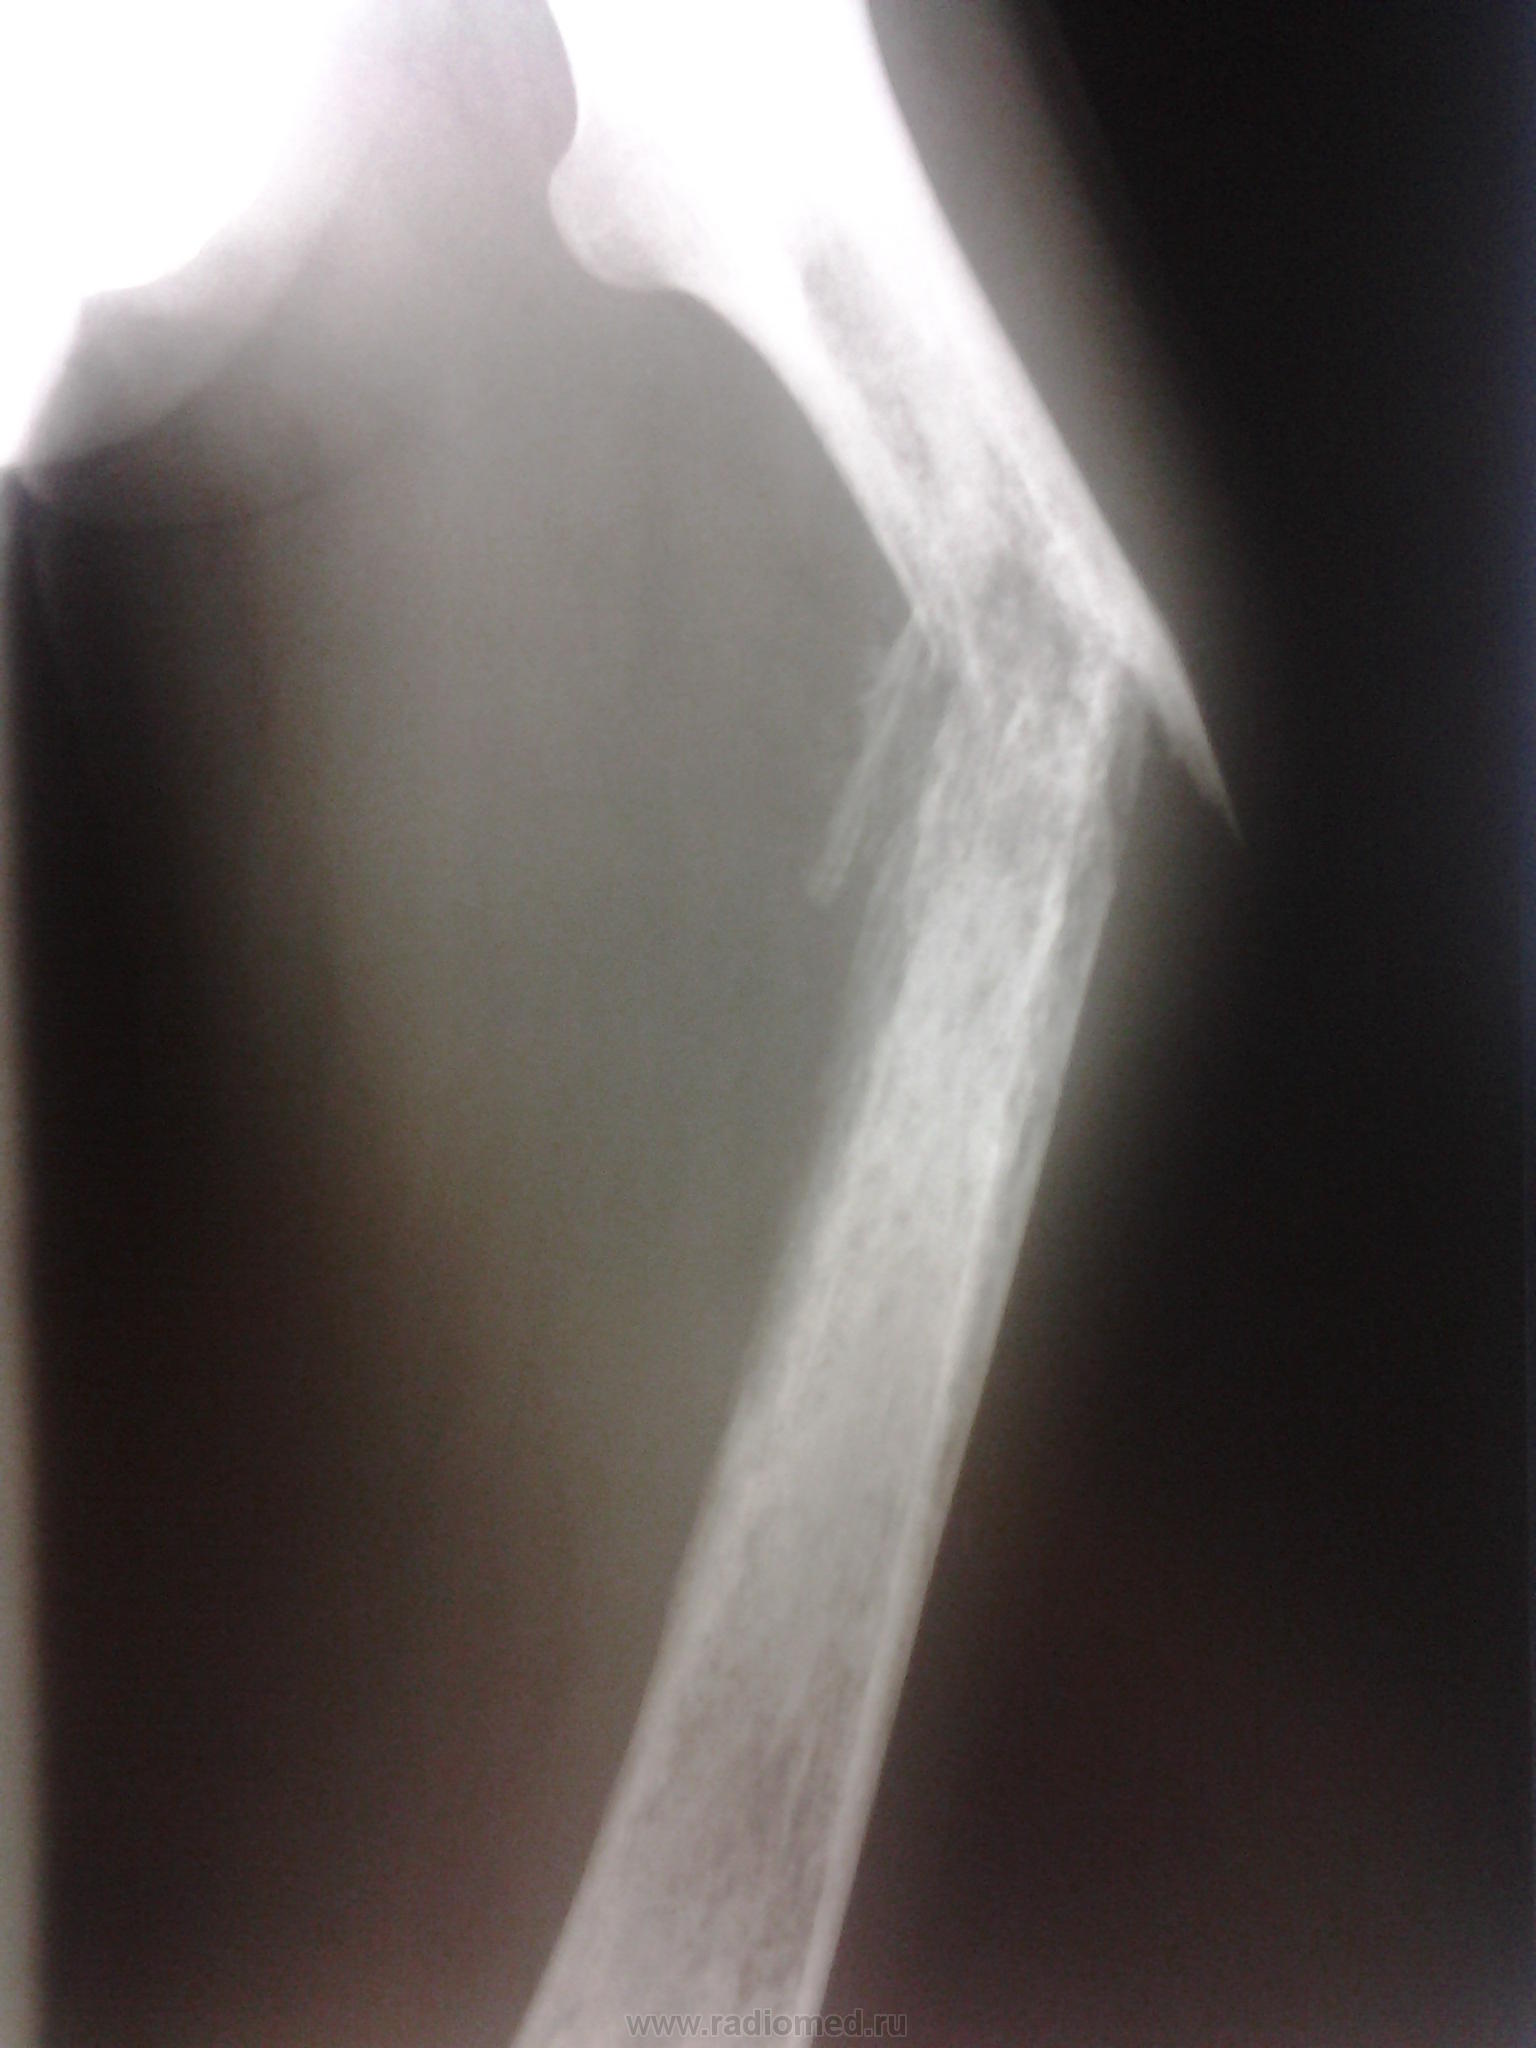

Замечено, что остеосаркома чаще всего развивается в тканях длинных трубчатых костей, к которым относится и бедренная кость. На ее долю выпадает основное количество диагностированных случаев описываемого заболевания – приблизительно в 80% всех диагностированных случаев остеогенных сарком был поражен дистальный конец бедренной кости (тот, который принимает участие в формировании коленного сустава). Такая статистическая закономерность касается всех возрастных групп, у представителей которых было выявлено описываемое заболевание.

На втором месте по поражению – метафиз. Так называют участок кости (в данном случае бедренной), который располагается между ее суставным фрагментом и диафизом (трубчатым участком). Сам же диафиз поражается наиболее редко – у каждого десятого пациента с описываемой патологией.

- рентгенологическое исследование – его информативность не всегда удовлетворяет, но метод позволяет выявить опухоль в месте развития остеосаркомы, а при ее прогрессировании – существенный дефект тканей. К тому же, рентгенологические аппараты имеются даже в небольших клиниках – с их помощью ставят предварительный диагноз, после чего есть смысл направить пациента на прохождение более информативных методов исследования;

- компьютерная томография (КТ) – компьютерные срезы позволяют детально изучить структуру костной ткани в месте поражения;